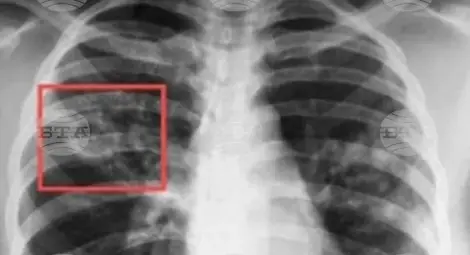

Прегледите ще включват анкетиране на желаещите, при оплаквания ще се прави рентгенова снимка, проба "Манту", а при нужда и микробиологично изследване за наличие на туберкулоза.